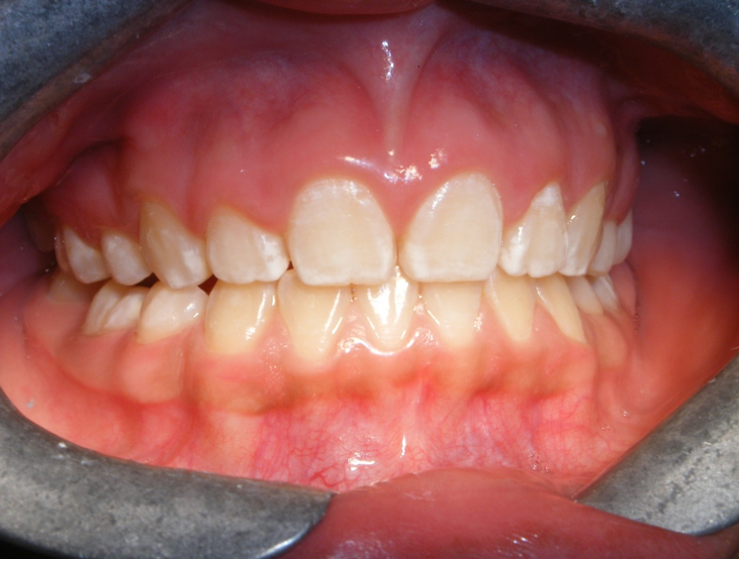

Mordida Cruzada anterior unidental